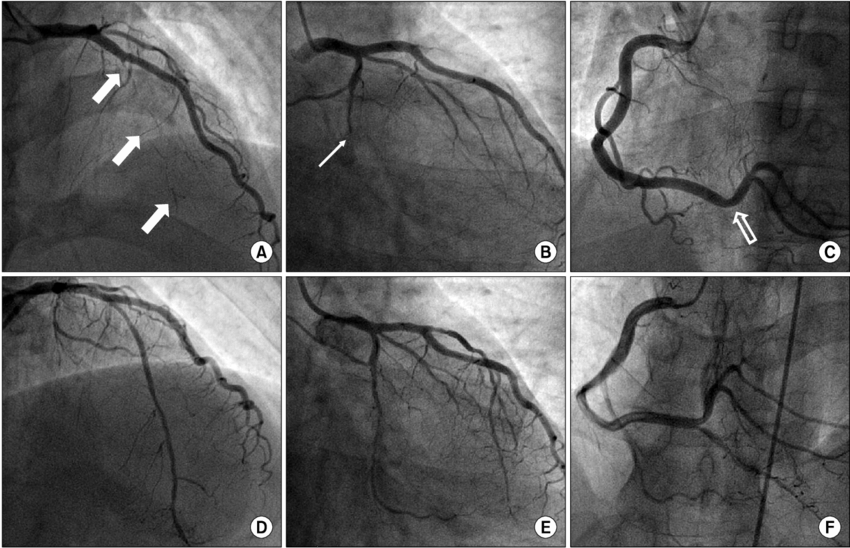

5. Coronary Angiography (Cardiac Catheterization)

Purpose: Provides a detailed view of the coronary arteries to confirm blockages.

Coronary angiography is the gold standard for detecting heart blockages. It is an invasive test that allows doctors to see the exact location and severity of the blockage.

Procedure:

- A catheter is inserted into a blood vessel (usually in the groin or wrist) and guided to the heart.

- A contrast dye is injected into the coronary arteries.

- X-ray imaging reveals the blood flow and identifies blockages.

Advantages:

- Highly accurate in diagnosing blockages.

- Allows for immediate treatment, such as angioplasty or stent placement, if needed.

Limitations: This test is invasive and carries risks like bleeding or infection, but it is essential for critical cases.